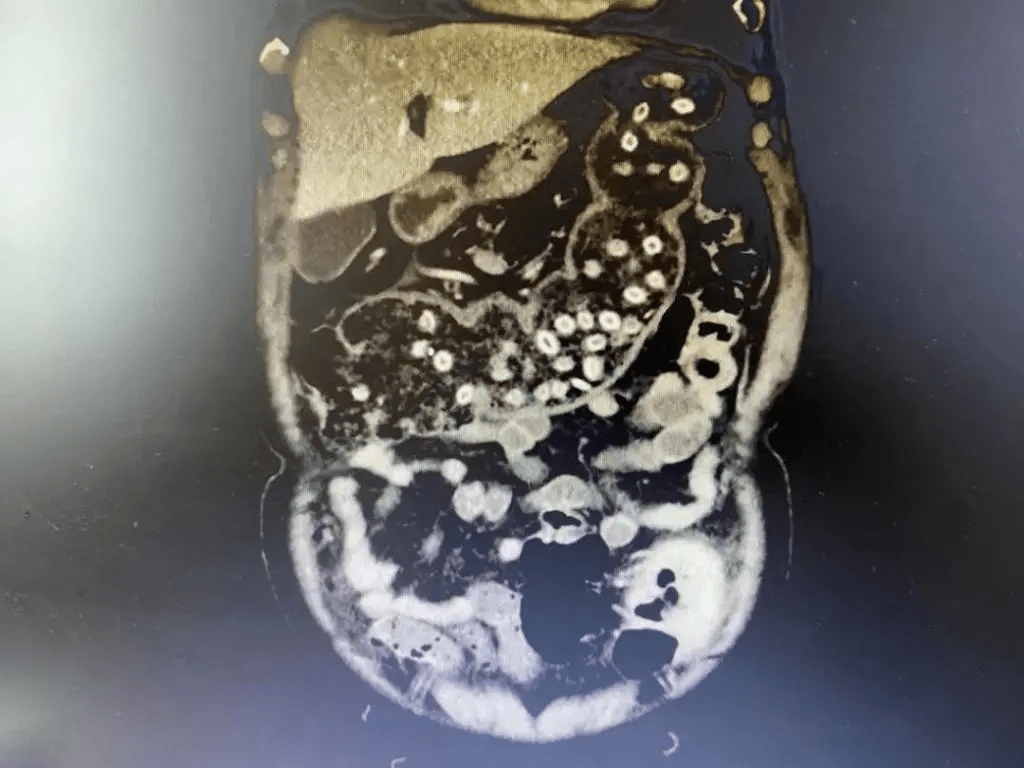

刘杰峰主任接诊后 , 给唐爹爹完善 CT 简直 " 惊呆了 "!一肚子密密麻麻的小 " 珠珠 " 仿佛连成一串 " 珍珠项链 " 了 。

文章图片